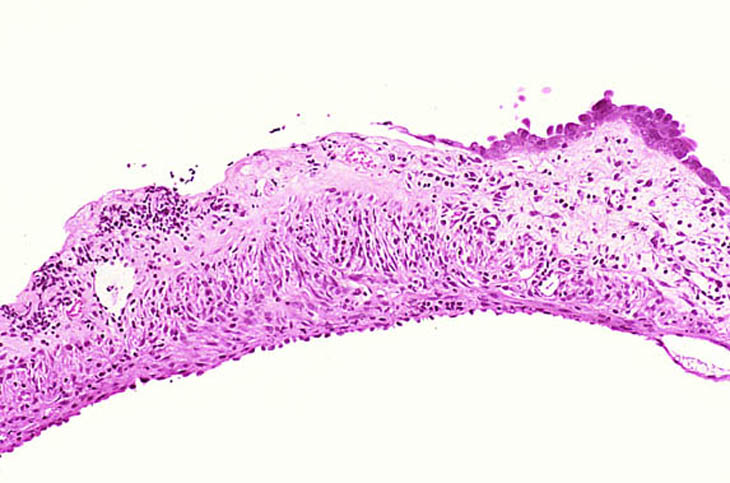

Chronic inflammation of the gallbladder with mucosal ulceration.